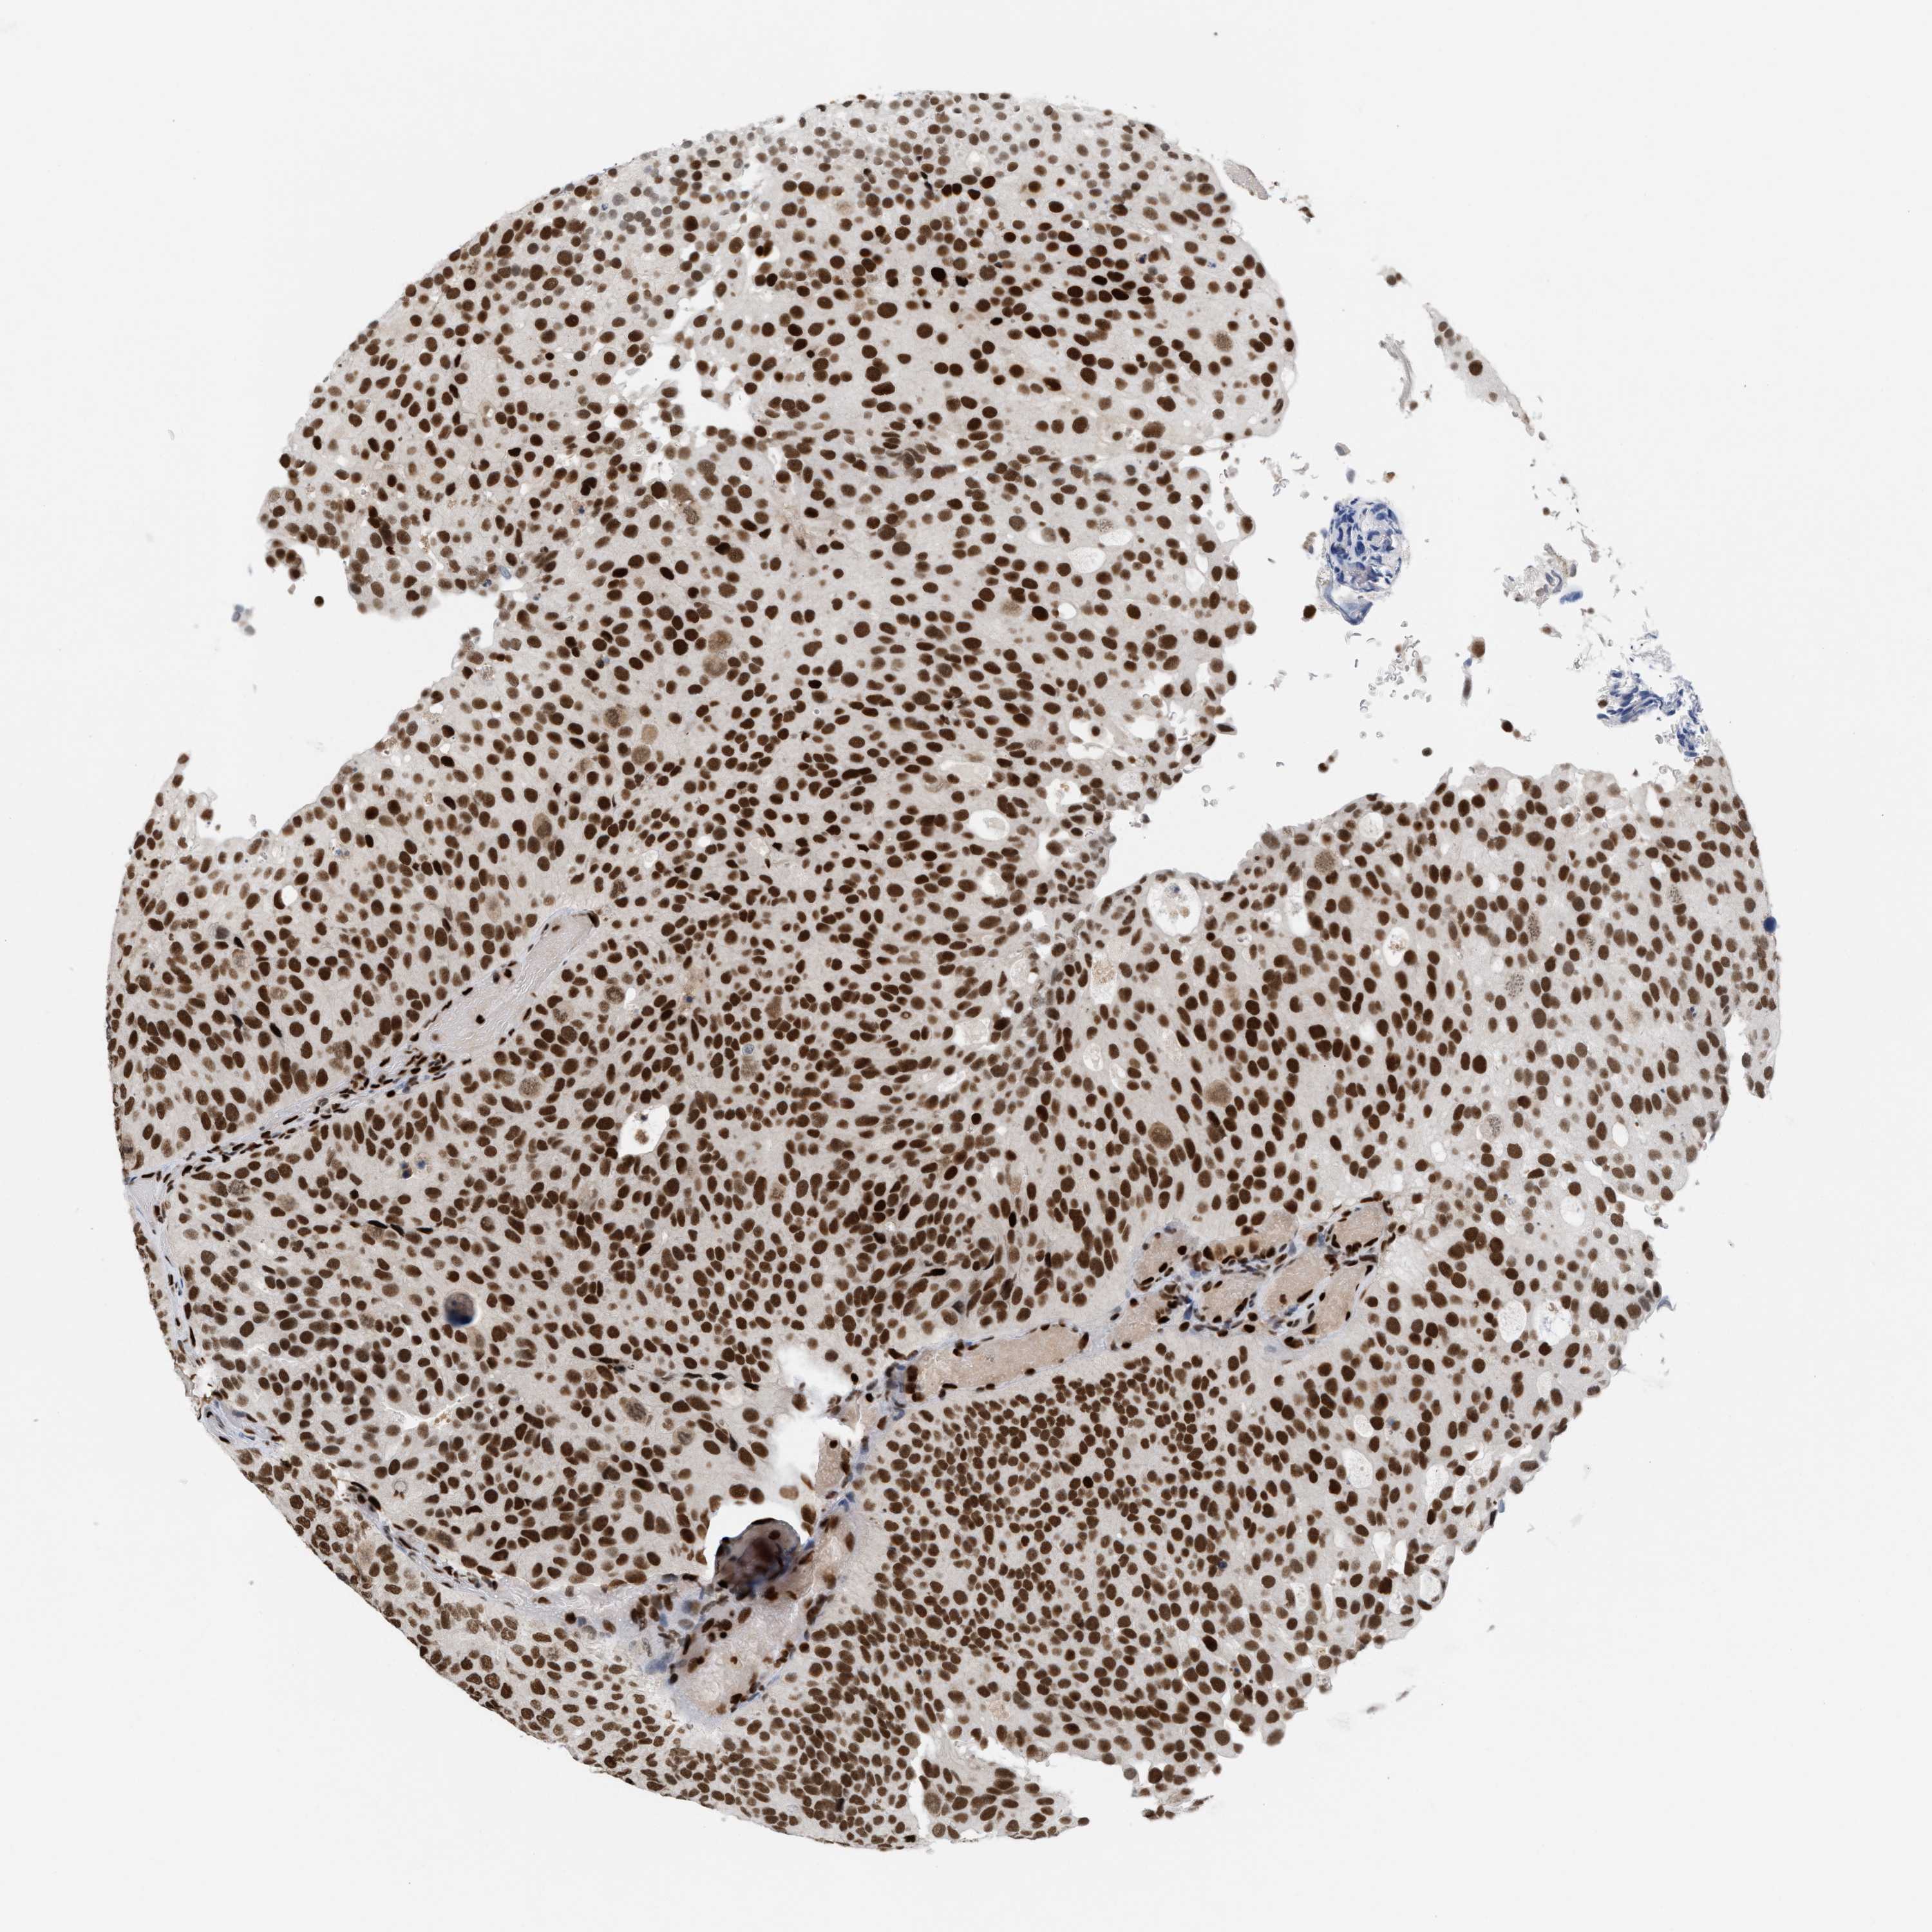

UROTHELIAL CANCER - Protein expressioni

A mouse-over function shows sample information and annotation data. Click on an image to view it in a full screen mode. Samples can be filtered based on level of antibody staining by selecting one or several of the following categories: high, medium, low and not detected. The assay and annotation is described here.

Antibody stainingi

Antibody staining in the annotated cell types in the current human tissue is reported as not detected, low, medium, or high, based on conventional immunohistochemistry profiling in selected tissues. This score is based on the combination of the staining intensity and fraction of stained cells.

Each image is clickable and will lead to virtual microscopy that enables deeper exploration of all samples and also displays staining intensity scores, fraction scores and subcellular localization as well as patient and tissue information for each sample.

Antibody HPA022961

Urothelial carcinoma, Low grade

Urothelial carcinoma, High grade